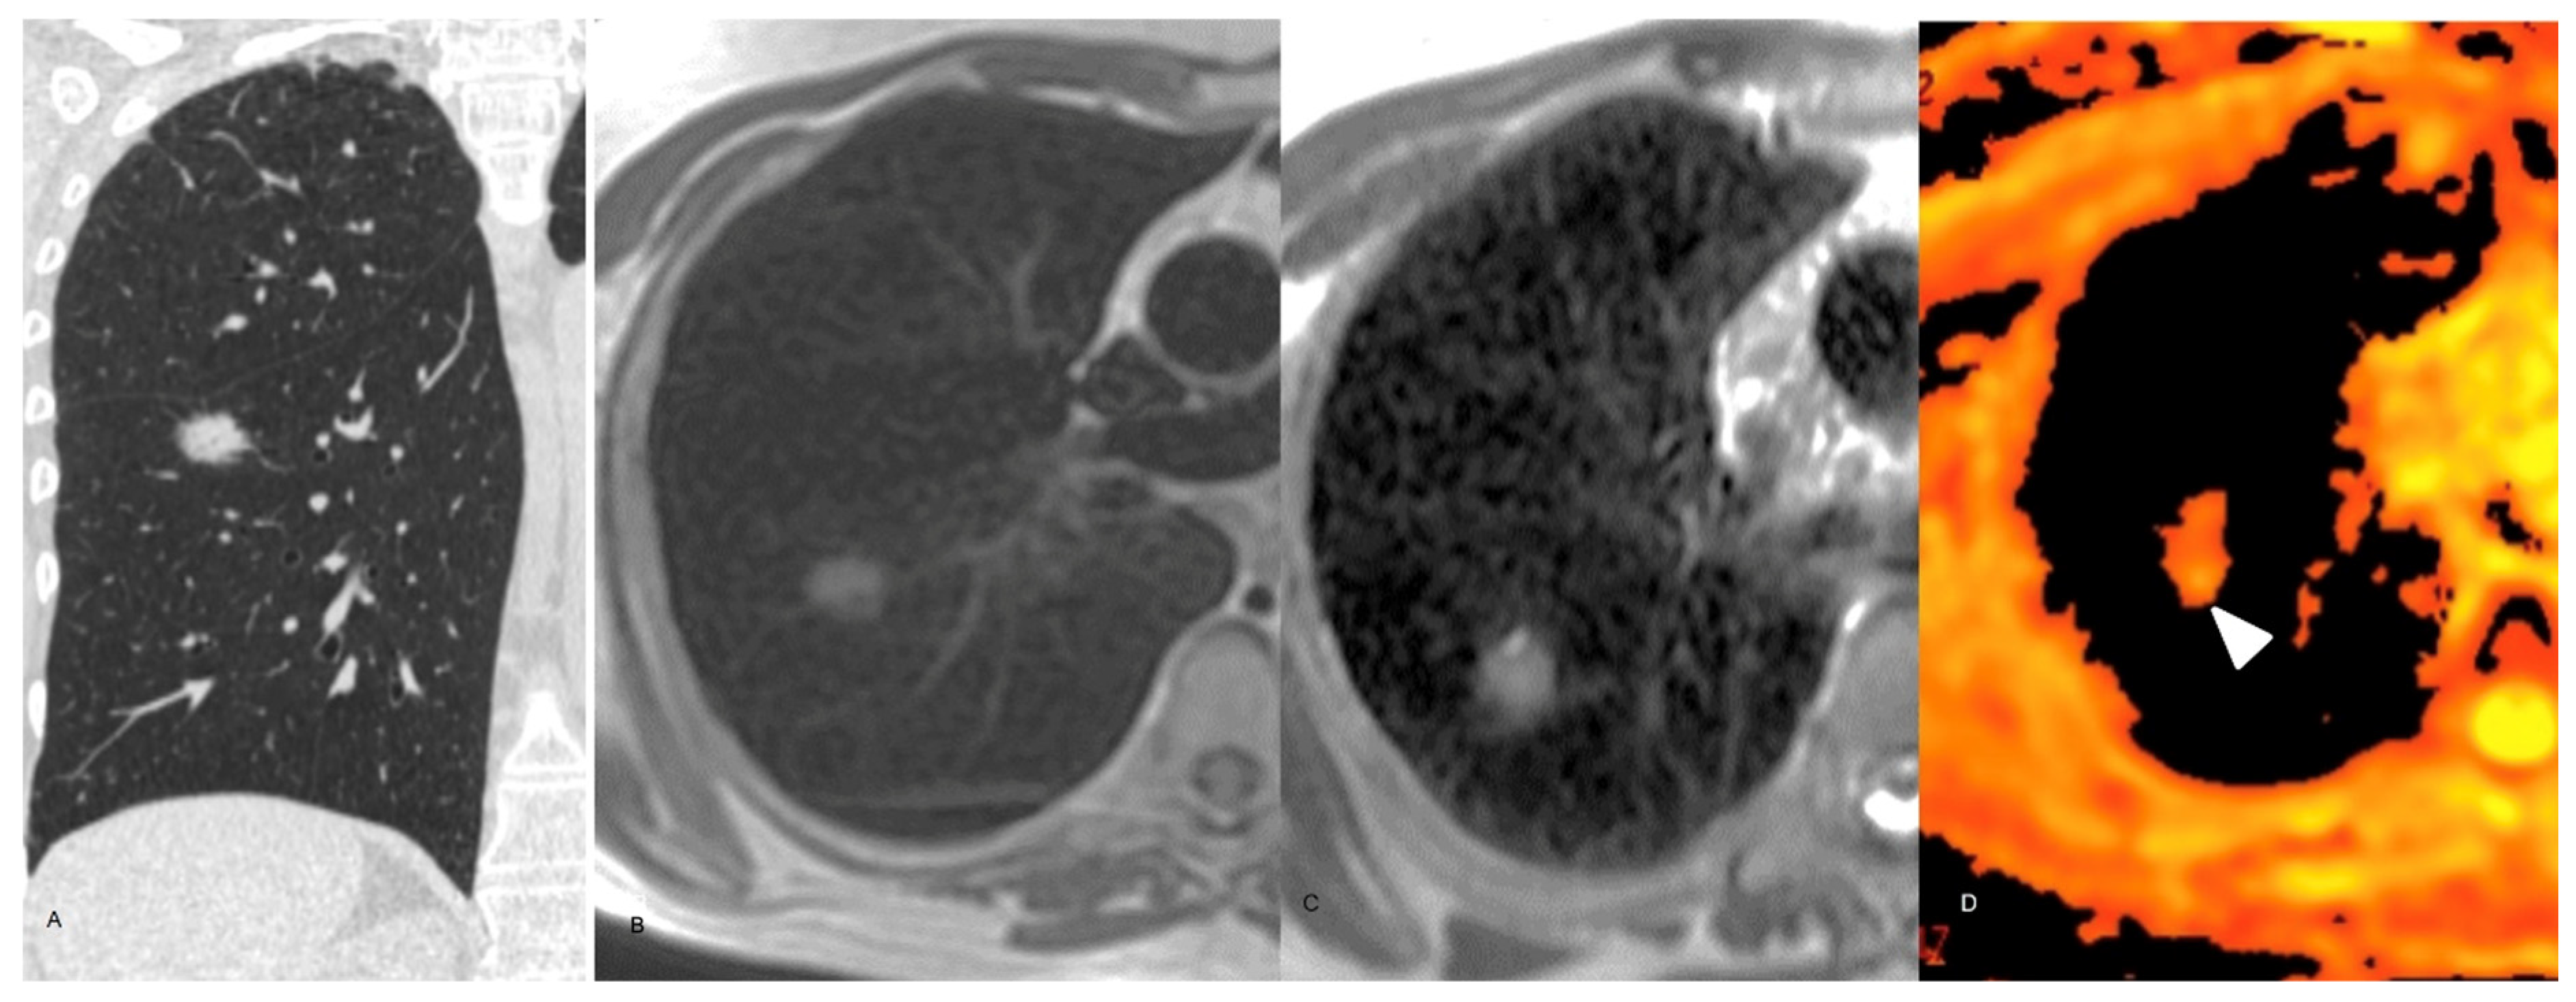

3.2. MR Findings